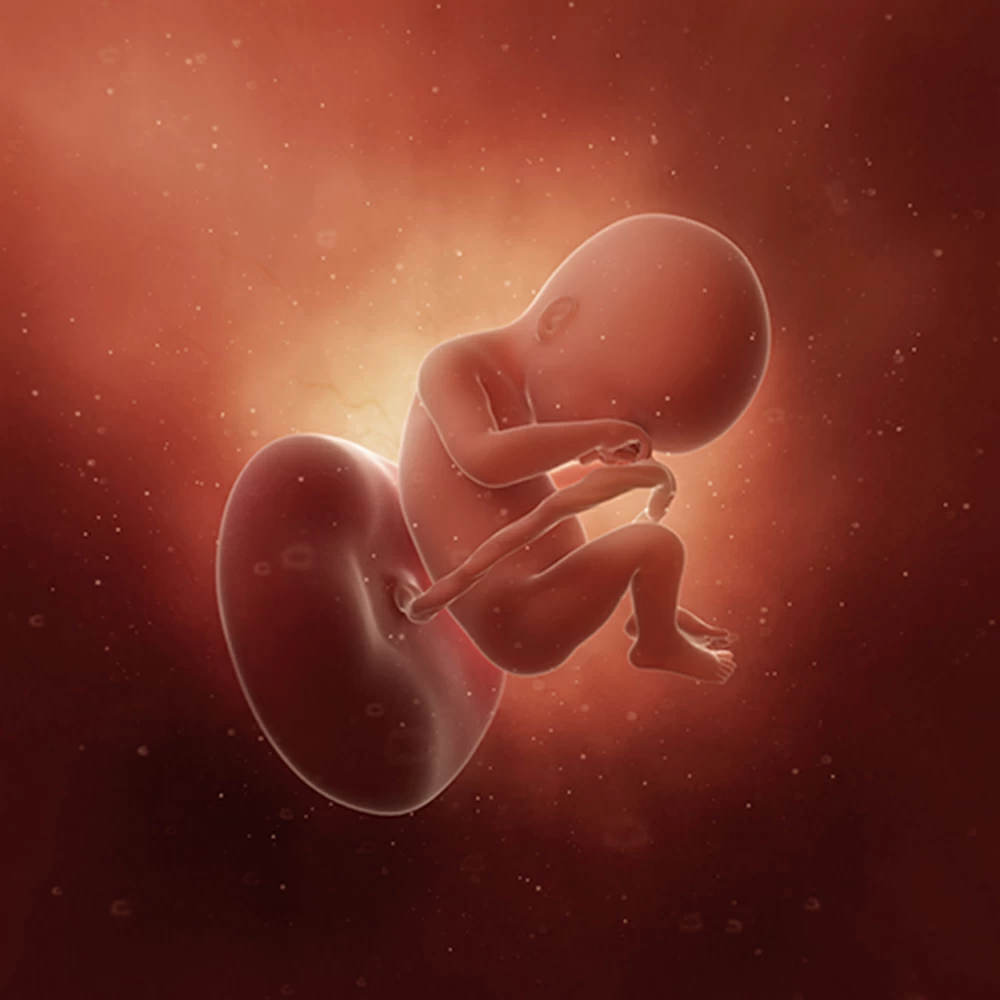

Неделя № 21

Масса тела вырастает до 380 грамм, длина плода – до 27 см.

Плод свободно перемещается в полости матки: ложится вниз головой или ягодицами, поперек матки. Может играть пуповиной, отталкиваться руками и ногами от стенок матки.

Изменяется режим сна и бодрствования. Сейчас плод меньше проводит времени во сне (16-20 часов).